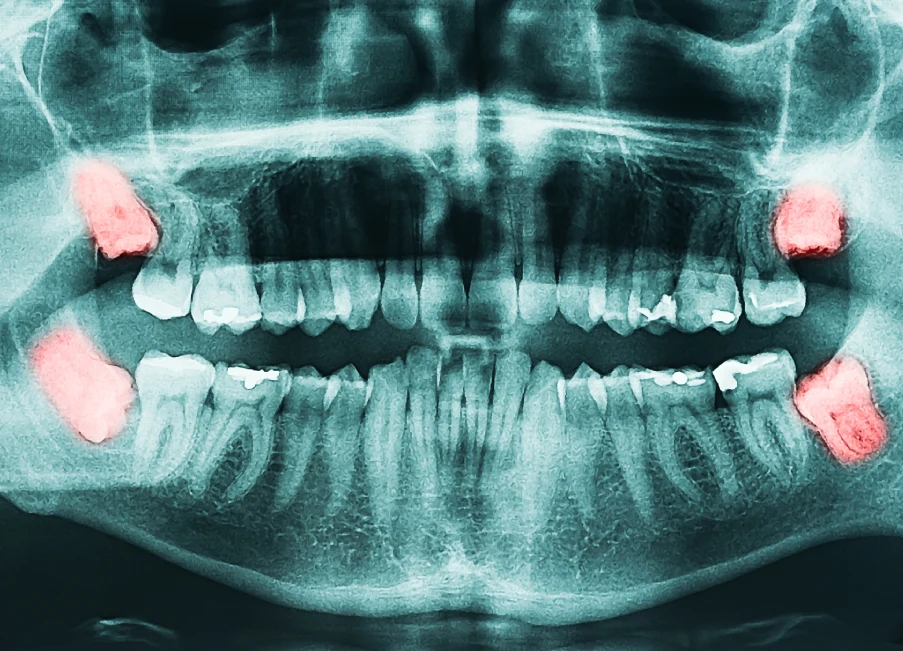

SeptemberDental Implants

The Gold Standard for Tooth Replacement: Dental Implants Losing a tooth—whether from injury, decay, or periodontal disease—affects much more than appearance. It can interfere with proper chewing, alter speech, and …